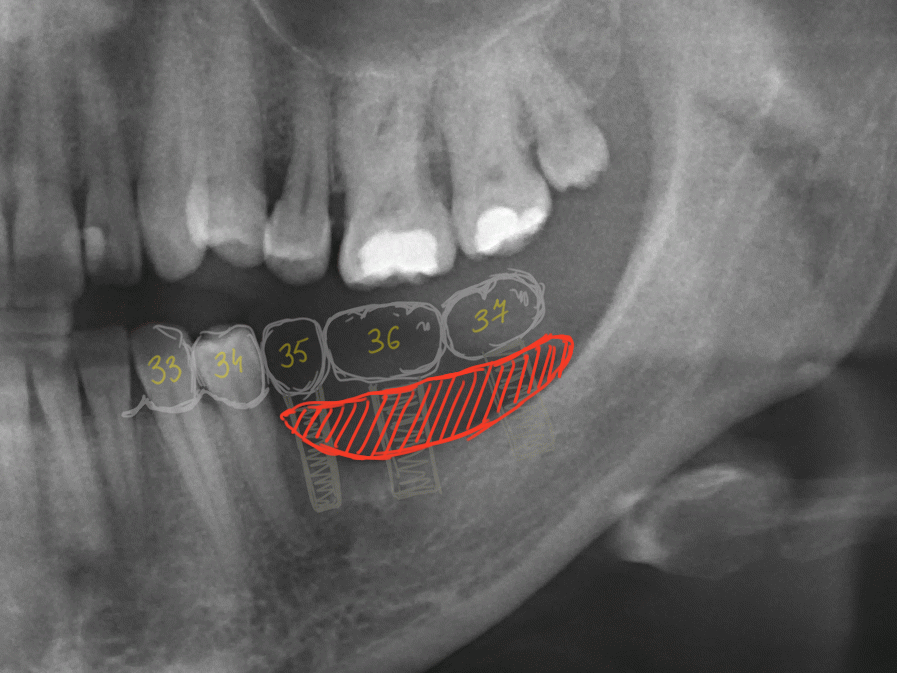

Через год после травмы, девушка обратилась в нашу клинику для восстановления отсутствующего зуба. К тому моменту у нее уже был временный съемный протез, изготовленный в вышеозначенном стоматологическом кабинете, ну и, вот какая клиническая картина:

Хочу спросить вас, уважаемые друзья, можно ли в таком состоянии и при таких объемах альвеолярного гребня поставить имплантат в область отсутствующего зуба? Безусловно, можно. Для этого нужно просто взять имплантат потоньше и поставить его подальше, в сторону неба — и он нормально интегрируется.

Возможно ли получить на подобном импланте более-менее приемлемый эстетический и функциональный результат? Вряд ли. Если за пределами эстетически значимой зоны мы можем пойти на эстетические компромиссы (все равно никто не увидит), то проблемы с эстетикой в области передней группы зубов… да еще у девушки…. так можно человеку всю личную жизнь испортить.

Поэтому, несмотря на возможность установить имплантат потоньше и подальше, мы планируем в ходе имплантологического лечения увеличение объема альвеолярного гребня до приемлемого уровня с помощью остеопластических процедур. Ориентиром «приемлемого уровня» является симметричный центральный резец. В идеале, вокруг нашего импланта должен быть абсолютно такой же объем тканей — только так мы можем добиться эстетического результат лечения.